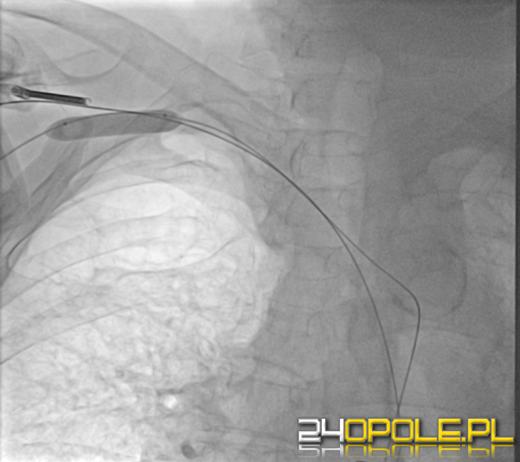

W ubiegłym tygodniu zespół specjalistów Uniwersyteckiego Szpitala Klinicznego w Opolu w składzie: dr hab. Jerzy Sacha, dr Krzysztof Krawczyk, Izabela Wójcik, Małgorzata Demkowicz, Anna Kwiatkowska wykonał skomplikowany zabieg kardiologiczny- zabieg angioplastyki z urządzeniem wspomagającym krążenie (Impella), wprowadzonym przez kończynę górną bez chirurgicznego rozcinania tkanek.

Do tej pory w Polsce nie wykonano zabiegu poprzez wprowadzenie Impelli przez rękę (dotychczas wprowadzano ją przezskórnie przez kończyny dolne), a na świecie tylko pojedyncze ośrodki przeprowadzają podobne operacje. Konieczność takiego leczenia wynikała z faktu, że serce chorego było skrajnie słabe i wymagało wsparcia, a dodatkowo jego tętnice w nogach były pozamykane przez miażdżycę.

Zabieg zakończył się sukcesem i 69-letni chory czuje się dobrze.

Otwiera to nowe perspektywy leczenia bardzo ciężko chorych pacjentów, którzy do tej pory byli dyskwalifikowani od operacji - komentuje dr hab. Jerzy Sacha. - Przełamaliśmy pewne bariery, do czego potrzeba było odwagi i świetnego przygotowania całego zespołu.